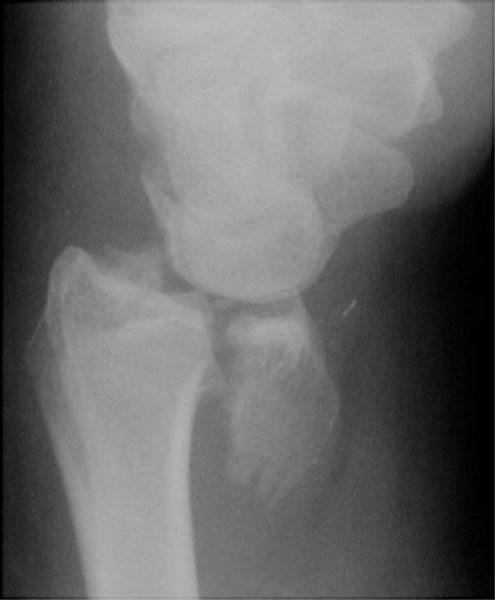

Return to Reverse Barton Fracture